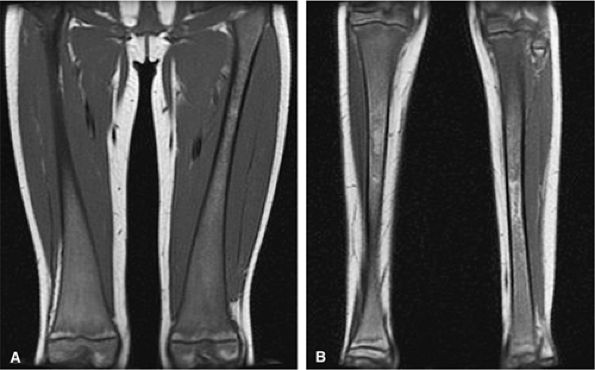

FIGURE 13.74 ● Gaucher disease involving the appendicular skeleton. Low-signal marrow infiltration is noted on a coronal image of the femurs (A) and lower legs (B). Extension into the epiphysis and distal skeleton is characteristic of advanced disease.

FIGURE 13.76 ● Undertubulation of the distal femurs causes characteristic Erlenmeyer flask deformity (arrows), as shown on an anteroposterior radiograph of the knees.